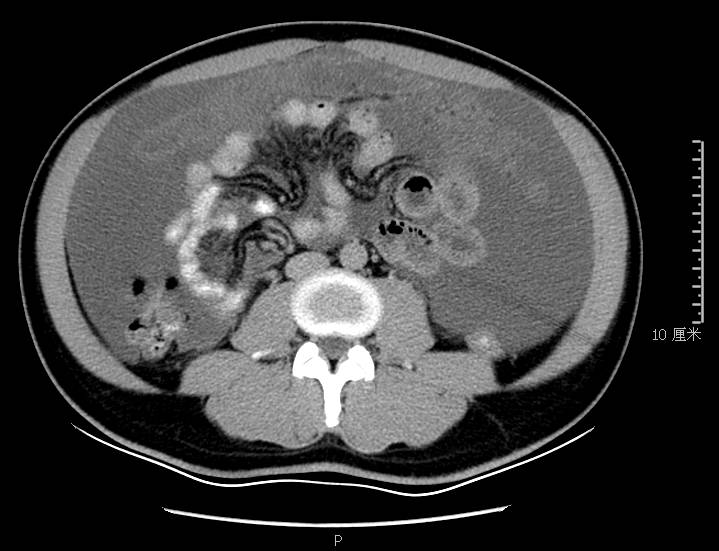

全腹CT:(1)结合病史斟酌腹膜炎(见图2A),大量腹水;(2)右骼窝区管状样结构,斟酌阑尾扩张(见图2B);(3)肝脏多发小囊肿(见图2C);(4)肝内胆管轻度扩张,建议隔期复查。

图2a大网膜成饼状(CT腹腔横断图象上出现肠曲被前面及两侧的肿瘤组织限制在中央

本例确诊后对B超及CT再次回顾发现:腹腔、盆腔可见不均质中强回声包块,部分呈囊实状,腹膜增厚,大网膜成饼状(如图2A)和肝周可见不均质中强回声弧形压迹、脾周可见不均质中强回声包饶,肝脏成扇贝样改变(如图2C),但在诊断报告中未提及。有学者发现mantle和scalloping(如图2A,2C)在PMP中具有代表性,且mantle较scalloping更为常见,若mantel征同时伴有大小不一的囊性改变,则更具诊断价值。

图2c肝脏成扇贝样改变(肝脏由于受肿瘤实质性或囊性组织压迫而其实质却未受侵犯,于是在一处或多处呈下凹状或扇形皱褶状(scalloping)